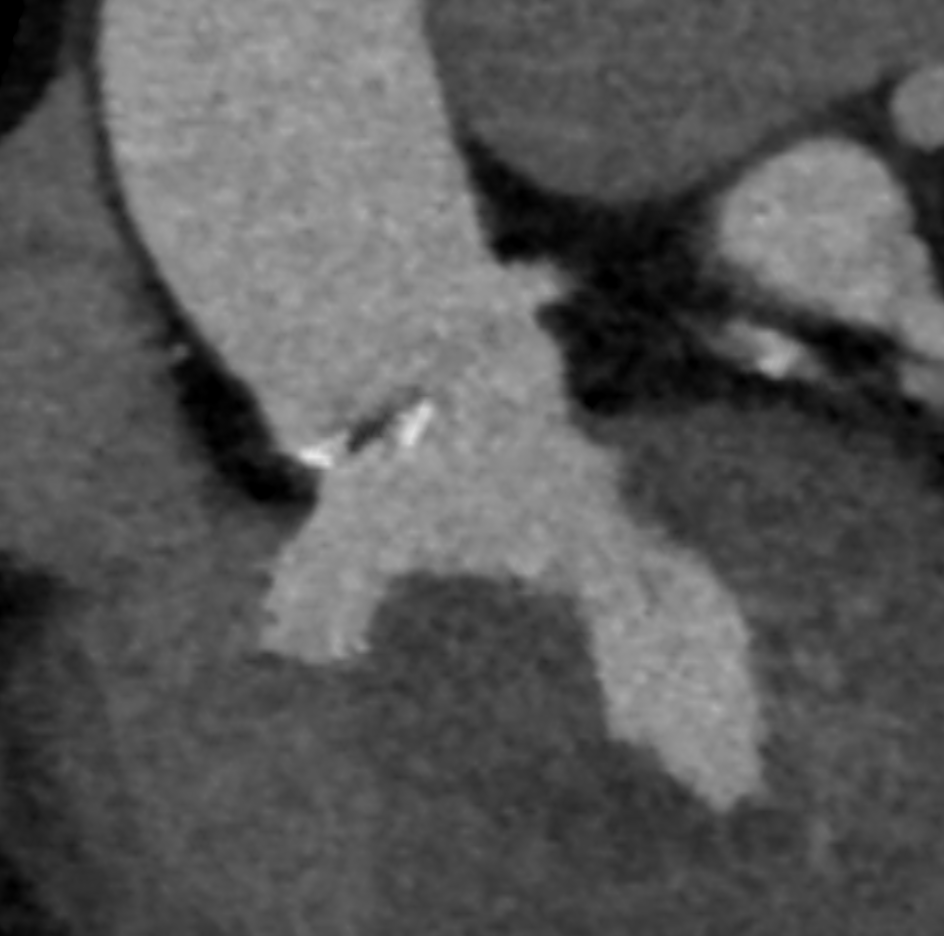

CT评估: